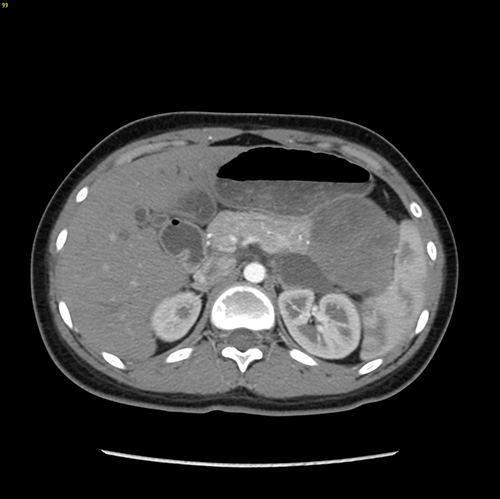

胰体尾实性假乳头状瘤---腹腔镜胰体脾切除